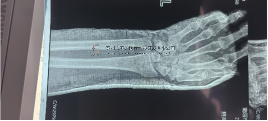

值得一提的是,不斷迭代的CO接骨手術(shù)機(jī)器人在大會中備受關(guān)注。該設(shè)備將人工智能技術(shù)融入傳統(tǒng)骨科手術(shù)中,實(shí)現(xiàn)了從理論到實(shí)踐的跨越,顯著提升了手術(shù)精準(zhǔn)度和患者治療效果,為廣大患者帶來了福音。